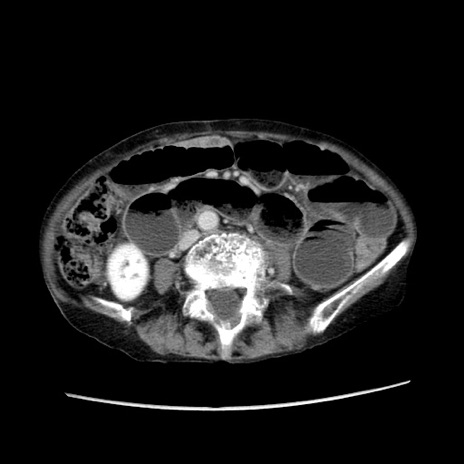

症例25(横断像)

【症例】80歳代女性

【主訴】胸のつかえ感

【現病歴】約9時間前に食後から胸のつかえた感じあり、嘔吐あり、来院。

【既往歴】胃癌(全摘)、胆摘、虫垂炎

【身体所見】心窩部に圧痛あり、反跳痛なし。

【データ】WBC 5700、CRP 0.05